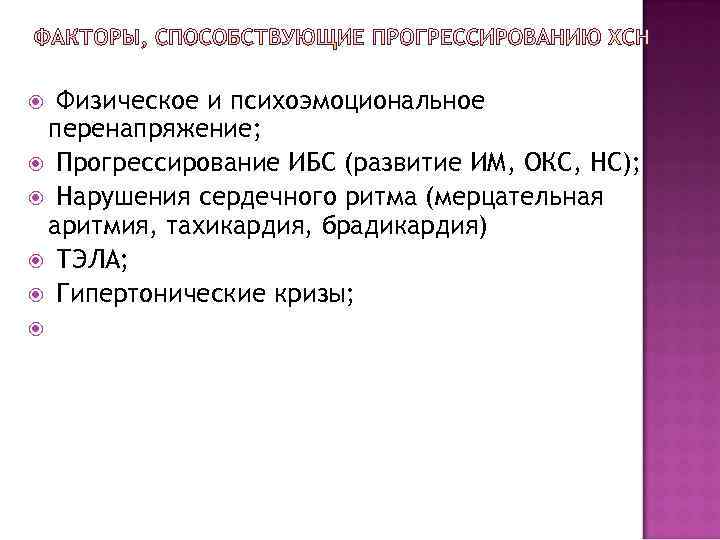

Физическое и психоэмоциональное перенапряжение; Прогрессирование ИБС (развитие ИМ, ОКС, НС); Нарушения сердечного ритма (мерцательная аритмия, тахикардия, брадикардия) ТЭЛА; Гипертонические кризы;

Физическое и психоэмоциональное перенапряжение; Прогрессирование ИБС (развитие ИМ, ОКС, НС); Нарушения сердечного ритма (мерцательная аритмия, тахикардия, брадикардия) ТЭЛА; Гипертонические кризы;